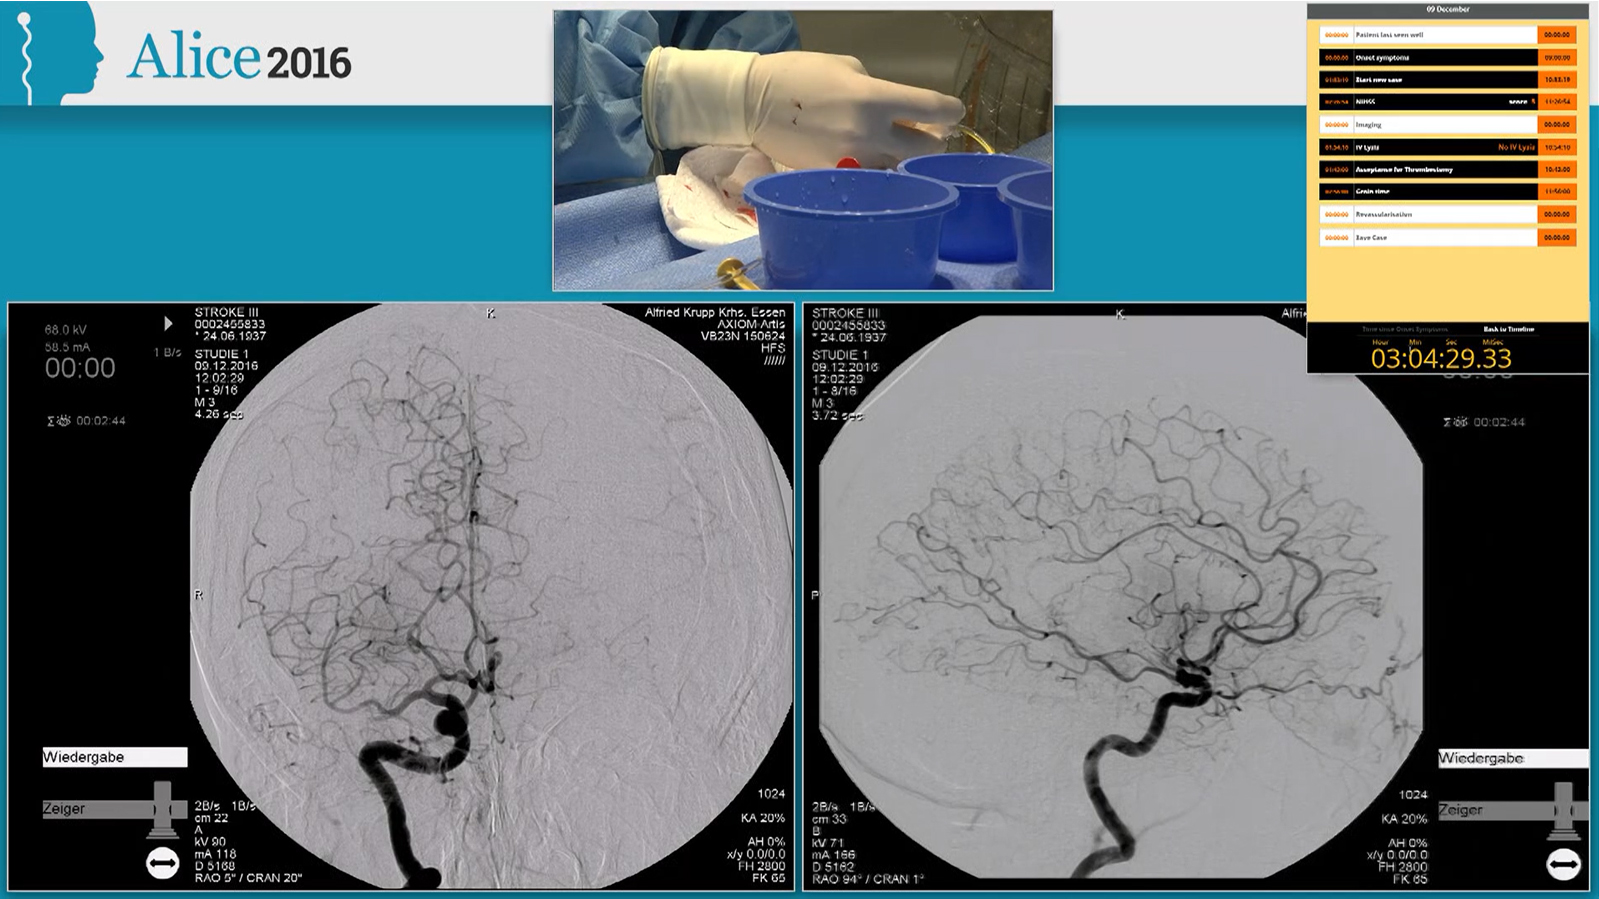

M1 occlusion, thrombectomy with Solitaire and balloon guiding catheter